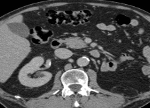

La tomografia computerizzata (TC o CT, dall’inglese Computed tomography, o TAC, Tomografia assiale computerizzata) è una tecnica radiologica con la quale si ottengono immagini di sezioni del corpo umano, evitando le sovrapposizioni delle diverse strutture più generalmente utilizzate nella radiologia tradizionale.

La tecnica si fonda sulla ricostruzione, operata da un calcolatore, della densità dei diversi tessuti del corpo umano, attraversati da un fascio di radiazioni X. Lo scanner TC è costituito essenzialmente da un tubo a raggi X e da rivelatori.

Il tubo radiogeno produce un fascio di raggi X che passa attraverso il paziente. Questo fascio viene catturato dai rivelatori e ricostruito per creare un’immagine di valore diagnostico.

La TC è caratterizzata da una elevata risoluzione di contrasto; tuttavia, può risultare difficile distinguere il fegato dalle strutture vascolari in esso contenute. Per ovviare a questo problema, si ricorre all’iniezione di un mezzo di contrasto, a base di iodio e, solitamente, iniettate per via venosa.

Il paziente si sdraia su un tavolo comandato da una consolle centrale di controllo. La regione corporea viene posta all’interno dell’apparecchio TC munito di una ampia apertura. Le immagini vengono acquisite in pochi secondi e al paziente viene chiesto di rimanere immobile e di non respirare nel caso di esami del torace e dell’addome.

Tac Addome Completo, a cosa serve e come si esegue: L’esame TAC Addome Completo (superiore e inferiore) è lo studio degli organi e dei vasi

Colonscopia Virtuale, cos’è? La Colonscopia Virtuale è una tecnica radiologica non invasiva, che consente di studiare la parete del colon simulando la colonscopia tradizionale. Si

Uro TAC, a cosa serve? Tac Uro è l’esame che consente lo studio delle vie urinarie (reni, ureteri, vescica), dopo iniezione del mezzo di contrasto